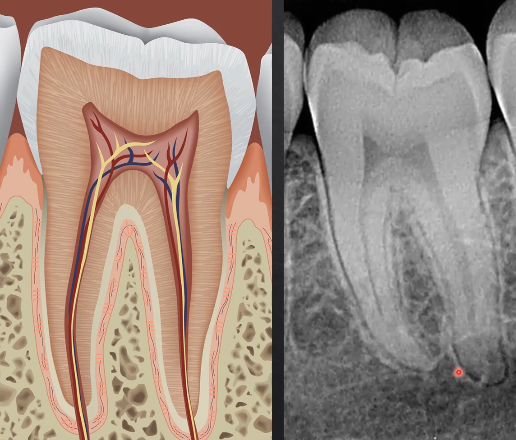

what can we determine from this radiograph?

the densest part of the tooth - enamel - appears most radiopaque as it absorbs/stops the most Xrays

dentine is more radiolucent

pulp is most radiolucent as its not calcified

silver/amalgam restorations absorb the most Xrays - most radiopaque